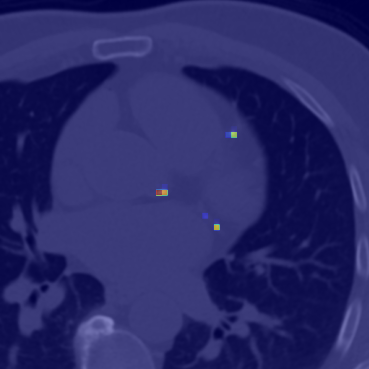

Coronary artery disease (CAD), one of the leading causes of mortality worldwide, necessitates effective risk assessment strategies, with coronary artery calcium (CAC) scoring via computed tomography (CT) being a key method for prevention. Traditional methods, primarily based on UNET architectures implemented on pre-built models, face challenges like the scarcity of annotated CT scans containing CAC and imbalanced datasets, leading to reduced performance in segmentation and scoring tasks. In this study, we address these limitations by incorporating the self-supervised learning (SSL) technique of DINO (self-distillation with no labels), which trains without requiring CAC-specific annotations, enhancing its robustness in generating distinct features. The DINO-LG model, which leverages label guidance to focus on calcified areas, achieves significant improvements, with a sensitivity of 89% and specificity of 90% for detecting CAC-containing CT slices, compared to the standard DINO model's sensitivity of 79% and specificity of 77%. Additionally, false-negative and false-positive rates are reduced by 49% and 59%, respectively, instilling greater confidence in clinicians when ruling out calcification in low-risk patients and minimizing unnecessary imaging reviews by radiologists. Further, CAC scoring and segmentation tasks are conducted using a basic UNET architecture, applied specifically to CT slices identified by the DINO-LG model as containing calcified areas. This targeted approach enhances CAC scoring accuracy by feeding the UNET model with relevant slices, significantly improving diagnostic precision, reducing both false positives and false negatives, and ultimately lowering overall healthcare costs by minimizing unnecessary tests and treatments, presenting a valuable advancement in CAD risk assessment.